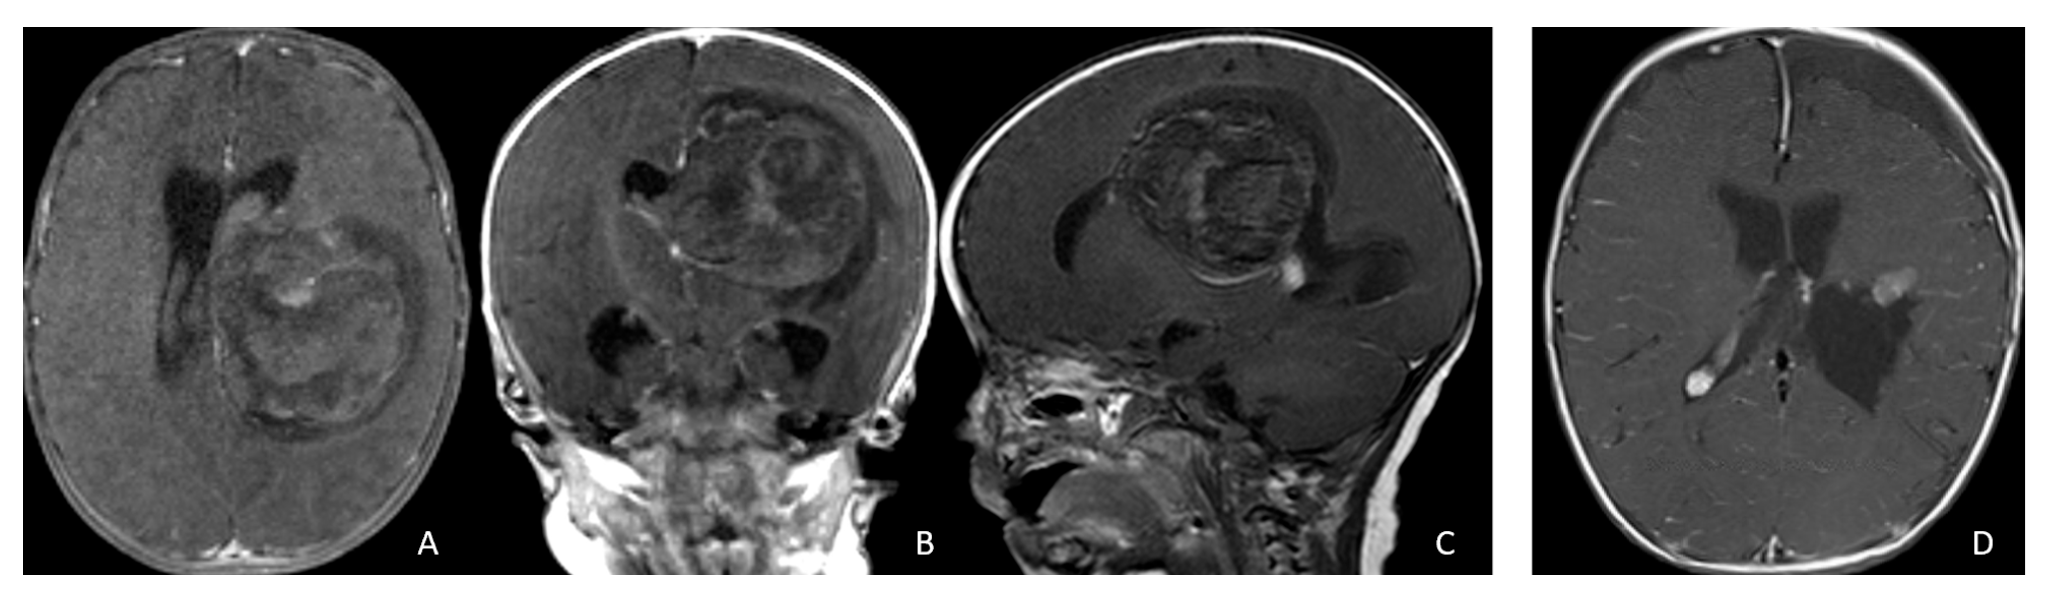

Tumor epicenters and patterns of extension were best delineated by operative observations combined with preoperative and postoperative imaging (Figure 1). Three patients had tumors involving both the temporal and frontal lobes that crossed the Sylvian fissure (Figure 2). Despite appearance of thalamic involvement on preoperative imaging, two patients had tumors primarily occurred in the basal ganglia, which became more evident on postoperative MRI (Figure 3). Additional hemispheric tumor extended into the thalamus. These lesions were resected via a trans-sylvian approach.

Figure 1.

Cerebral lobar ATRT. (A–D): 20-month-old boy with a parietal intraparenchymal ATRT. Preoperative axial images (A,B) and postoperative axial (C) and coronal (D) images confirm the intraparenchymal location following resection. (E–H): 26-month-old boy with a large heterogeneous frontal mass with multiple peritumoral cysts. Preoperative axial (E) and coronal (F) images, and postoperative axial (G) and coronal (H) images after gross-total resection support a frontal lobe origin despite of the basal ganglia origine as the preoperative imaging suggetsed.

Figure 3.

Basal ganglia ATRT. (A–D): Post contrast MR images ((A)-axial, (B)-coronal) of 13-month-old boy with deep seated ATRT. Note the solid tumor with peritumoral cysts at the basal ganglia with one cyst extending to the thalamus. Post-resection MR images ((C)-axial, ((D)-coronal) show the tumor resected cavity in the basal ganglia with the thalamus clear of tumor involvement. (E–H): Post contrast MR images ((E)-axial, (F)-coronal) of a 23-month-old boy with a large ATRT of deep temporal lobe and the insula extending to the basal ganglia. The tumor was predominantly in the basal ganglia as shown postoperative MR ((G)-axial, (H)-coronal).